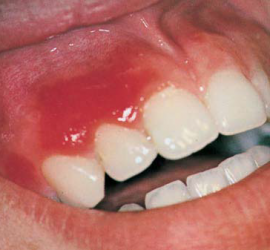

Ретроградный кариес. Кариозный процесс разрушает дентин со стороны пульпы. Наблюдается при наличии интактной, кариозной и пломбированной коронки, а также в случае гангрены пульпы кариозного и травматического происхождения. Со стороны полости пульпы идет процесс распада дентина за счет функции микроорганизмов и протеолитических ферментов. Ретроградный кариес может иметь место при хроническом пролиферативном […]